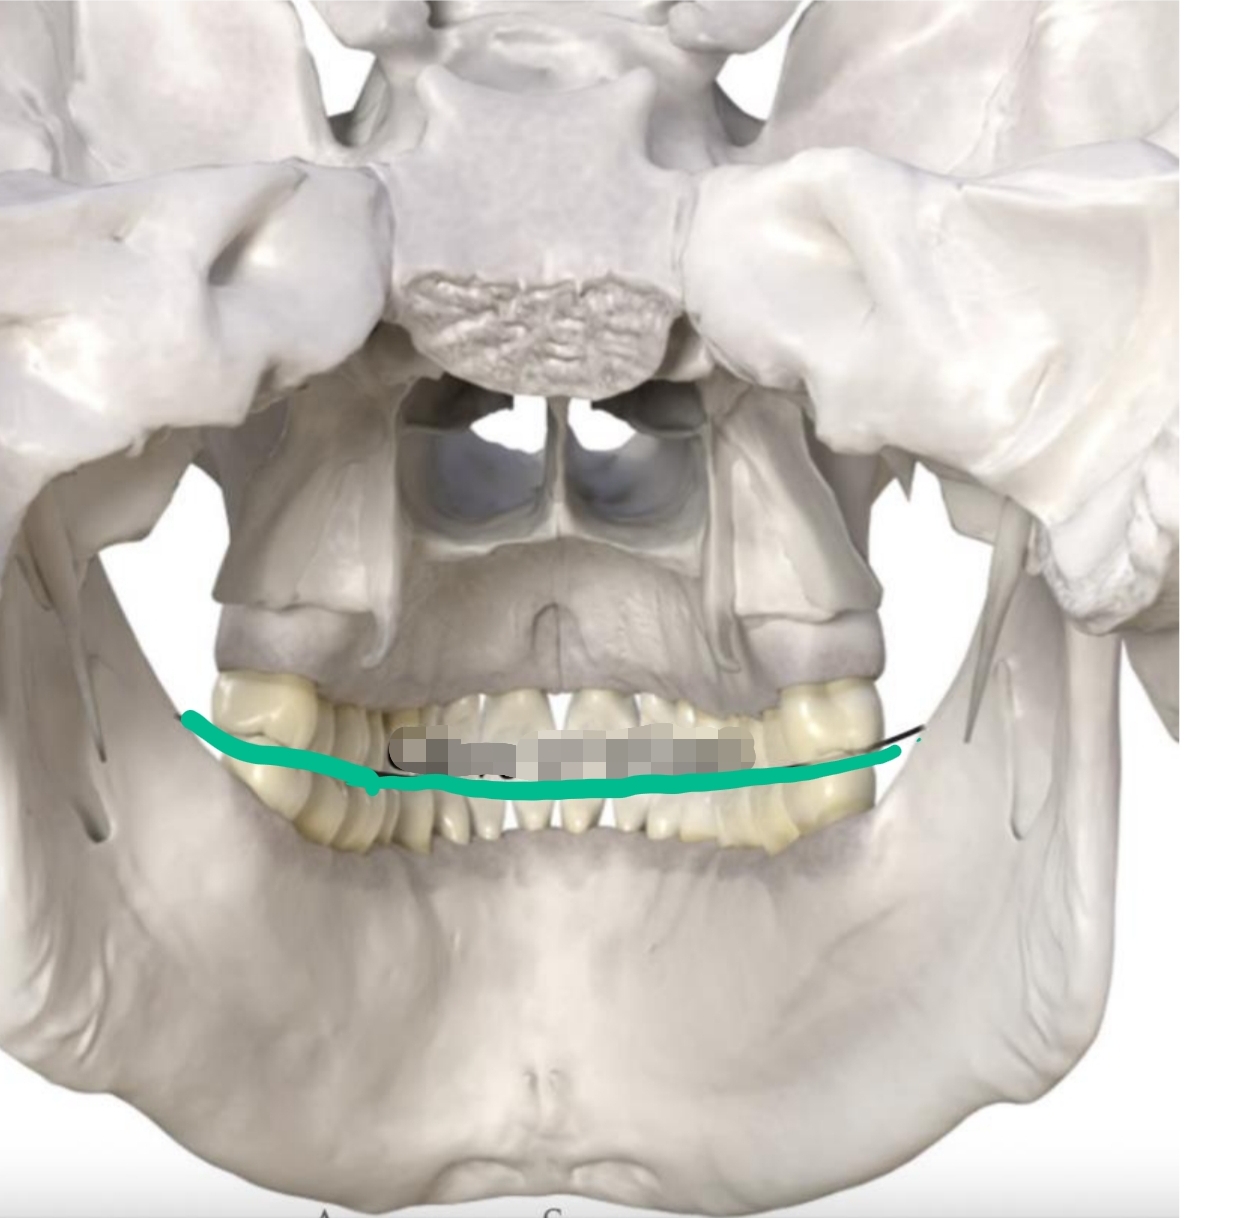

Anterior to posterior position (2 dimensional)

Begins at canines and follows posteriorly

Mandibular are concave

Maxillary are convex

Curve of Spee

Medial/lateral curvature of occlusal plane of posterior teeth

2-dimensional

Opposite direction of Curve of Spee

Allows for sphere of motion in chewing

Curve of Wilson